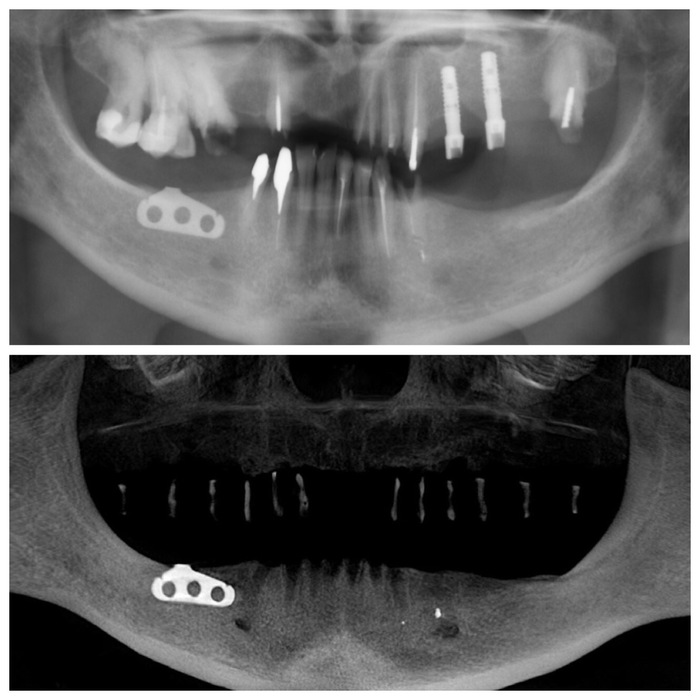

На панорамном снимке ниже по середине четко видны контрастные «белые цилиндры», это как раз и есть тот самый материал, которым были закрыты отверстия в верхнем съемном протезе. Сам протез не рентгеноконтрастен, поэтому его на снимке не видно.

Ну и на десерт. Узрите! Вот оно, ТВАРЬение! Об этом я и говорил, пластиночный имплантат с отверстиями в нем, в которые проросла костная ткань. Ну и сломанный «штырь», который был одной из опор для мостовидного протеза.

Итак, после того как были учтены результаты диагностики, консультация ортопеда и, что немаловажно, пожелания пациента (!), было принято решение о удалении всех зубов на верхней и нижней челюсти, в том числе установленных ранее имплантатах. Кроме пластиночного, его я оставил на десерт.

Единственным верным решением будет удаление пластиночного имплантата. Хотя… удаление мягко сказано. Его придется выпиливать. Что я имею в виду? А я имею в виду, ВЫ ПИ ЛИ ВАТЬ. После этого слова, где-то на горизонте кукла Билли верхом на своем велосипеде начинает медленно, но верно приближаться, а возможность адекватно воспринимать информацию потихоньку исчезает, согласитесь.

Как мы знаем, у пластиночных имплантатов отсутствует интеграция. Это значит, они не срастаются/не приживаются в кости. Держатся лишь механически. При формировании ложа под имплантат делается «траншея» вдоль альвеолярного гребня, куда в свою очередь помещается данная пластина. Со временем в отверстия этого имплантата прорастает костная ткань. И получается что-то типа замка. Поэтому иным способом кроме как тем, что я указал выше удалить его не удастся. Вы скажете, а разве привычный, цилиндрический имплантат приходится удалять не таким же образом? Акей, теперь сравните площадь раны при удалении пластины около 2 см. в длину, и цилиндра, в среднем 4,5мм в диаметре. Есть разница? Более того, если по каким-то причинам, возникают проблемы с цилиндрическим имплантатом, то как правило, он либо не интегрировался (не сросся с костью), а следовательно, достать его можно и пальцами рук, либо произошла критичная убыль костной ткани вокруг имплантата, как в данном случае. Зачастую работа бормашины или ультразвукового наконечника сводится к минимуму, также, как и травма после манипуляции. Хотя, конечно, это никак не умаляет сложностей, которые связаны с восстановлением объема утраченной кости в этой области. Так как обычно остается внушительная «дыра».